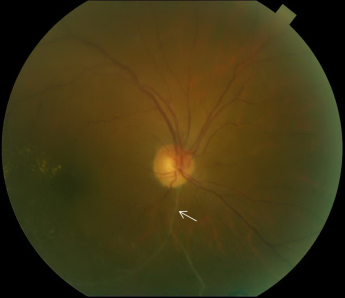

In patients with chronic BRVO, the intraretinal hemorrhages are absorbed and subsequent retinal vascular abnormalities develop in the distribution of the BRVO. The resulting changes include capillary nonperfusion, collateral formation, microaneurysms, sclerosed veins, and telangiectatic vessels (Figure 2).